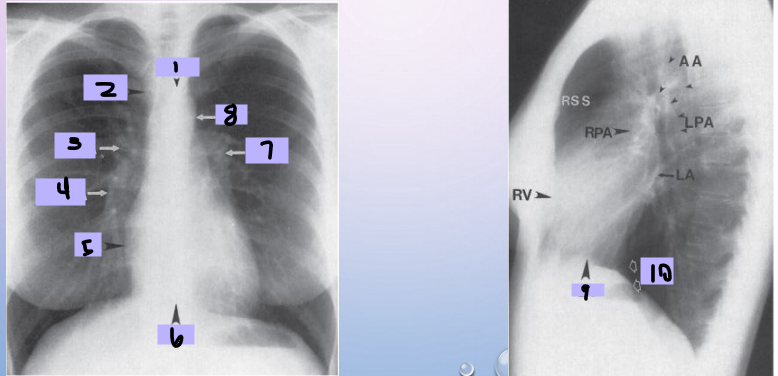

Aortic arch

#1

Superior vena cava

#2

Right pulmonary artery

#3

Right descending pulmonary artery

#4

Right atrium

#5

Right ventricle

#6

Left pulmonary artery

#7

Descending aorta

#8

Left ventricle

#9

Inferior vena cava

#10